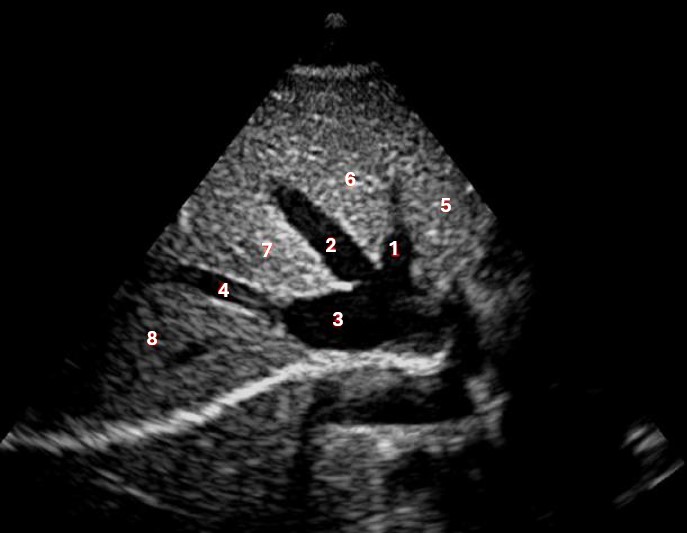

What lobe of the liver is indicated by #1?

Posterior right lobe

Which of the numbered vessels is part of the portal system?

2

What structure/vessel is indicated by #6?

Superior mesenteric artery

Which of the following structures is labeled #4?

Right hepatic vein

Which of the following structures is labeled #8?

What structure/vessel is indicated by #12?

Spine